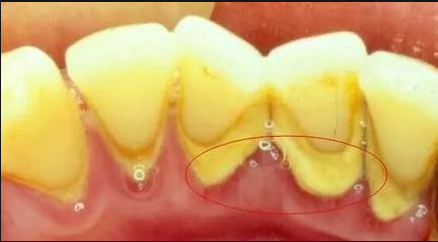

牙結石是由未及時清除的食物殘渣、細菌及其代謝產物組成的軟性菌斑逐漸鈣化形成的硬質沉積物。這個過程通常發生在牙齒頸部或齦緣下方,尤其是難以清潔的區域。隨著時間的推移,這些沉積物會變得越來越厚,并且難以通過刷牙等常規手段去除。

牙結石引起口臭的機制

細菌滋生:牙結石為厭氧菌提供了理想的生存環境,這些細菌分解食物殘渣時會產生揮發性硫化物(VSCs),如硫化氫和甲硫醇,這是口臭的主要來源。

炎癥反應:牙結石刺激牙齦組織,導致慢性炎癥即牙齦炎,甚至發展成更嚴重的牙周病。炎癥過程中產生的化學物質也會散發出異味。

阻塞唾液流動:大量牙結石堆積可能會部分阻斷唾液腺導管,減少唾液分泌。唾液具有天然的抗菌作用和清洗功能,其量減少后,口腔自潔能力下降,進一步加劇了口臭。